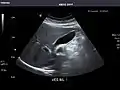

Renal ultrasonography

Ultrasound scan of a kidney (right side)

Ultrasonography of the kidneys is essential in the diagnosis and management of kidney-related diseases. The kidneys are easily examined, and most pathological changes in the kidneys are distinguishable with ultrasound.[7]